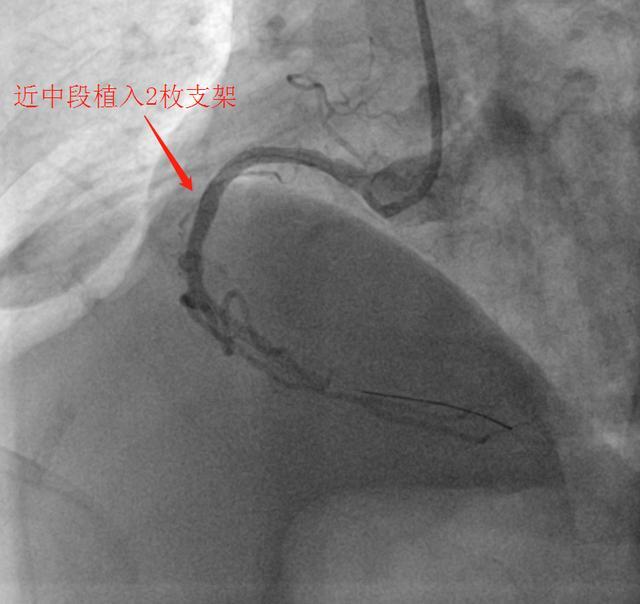

导管室内,医护人员凭借丰富的救治经验和精湛的操作技术,默契配合开展介入治疗。导丝精准穿过堵塞血管,支架顺利植入,闭塞的血管被成功开通,缺血的心肌重新获得血液灌注。从转运途中启动救治预案,到手术顺利完成,整个流程环环相扣、分秒必争,体现了高效有序的应急能力。

(▲术后)